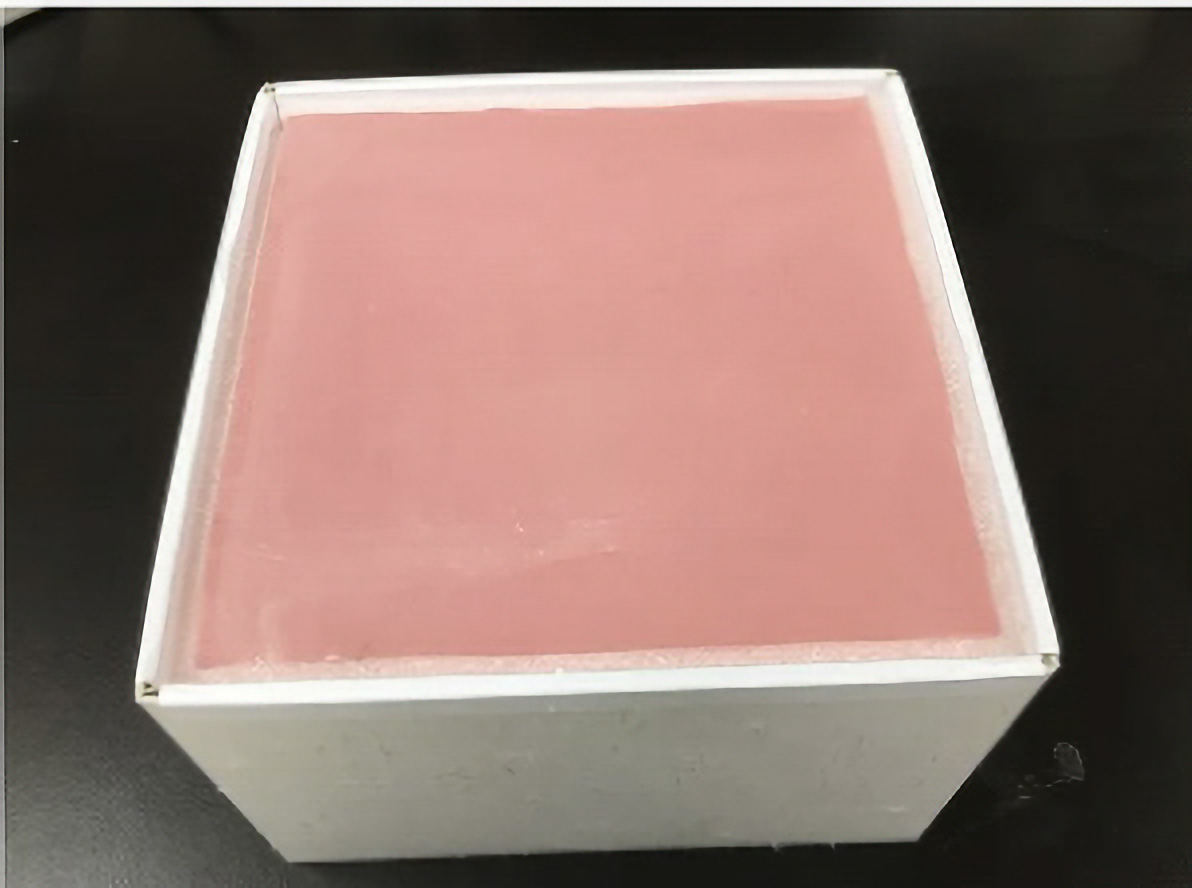

鶏卵を用いた簡易的腎生検シミュレーターが開発されていましたが、耐久性が低く長期保存が困難でした。そこで今回、幅広く適用されるモデルを目指して、スチレン系軟質樹脂を用いた新たな腎生検シミュレーターを開発しました。

鶏卵を用いた簡易的腎生検シミュレーターが開発されていましたが、耐久性が低く長期保存が困難でした。そこで今回、幅広く適用されるモデルを目指して、スチレン系軟質樹脂を用いた新たな腎生検シミュレーターを開発しました。

軟質エラストマー成型品/腎生検シミュレーター (製品名:JIN戦士君)